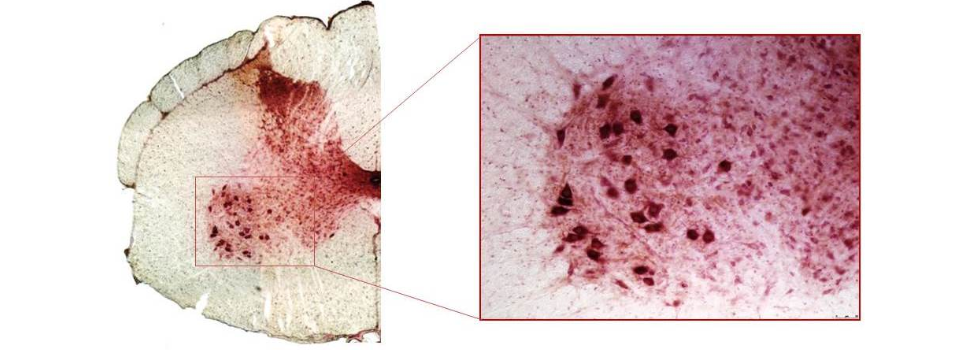

This image shows a monkey spinal cord, with a zoom on an area called the ventral horn. The dark red cells are motor neurons. The red shows presence of GFP, a protein that is not normally expressed by the animals. Its presence therefore demonstrates that we are able to transduce motor neurons with our gene therapy vector.

Our therapeutic strategy is to silence SOD1 following CSF-directed delivery of an AAVrh.10 expressing an artificial miRNA targeting all forms of SOD1 (wild-type and mutant). To achieve this, we have designed a miRNA called miR-SOD1, and we have shown that it mediates a strong silencing of SOD1 in cell culture. We then proceeded to test this candidate in adult ALS mice (SOD1G93A) to mimic as well as possible the human disease. We also tested it in non-human primates, to assess the efficacy in a model that is larger and closer to human. In monkeys, we demonstrated that we are able to efficiently target the motor neurons (see image on top of this page).